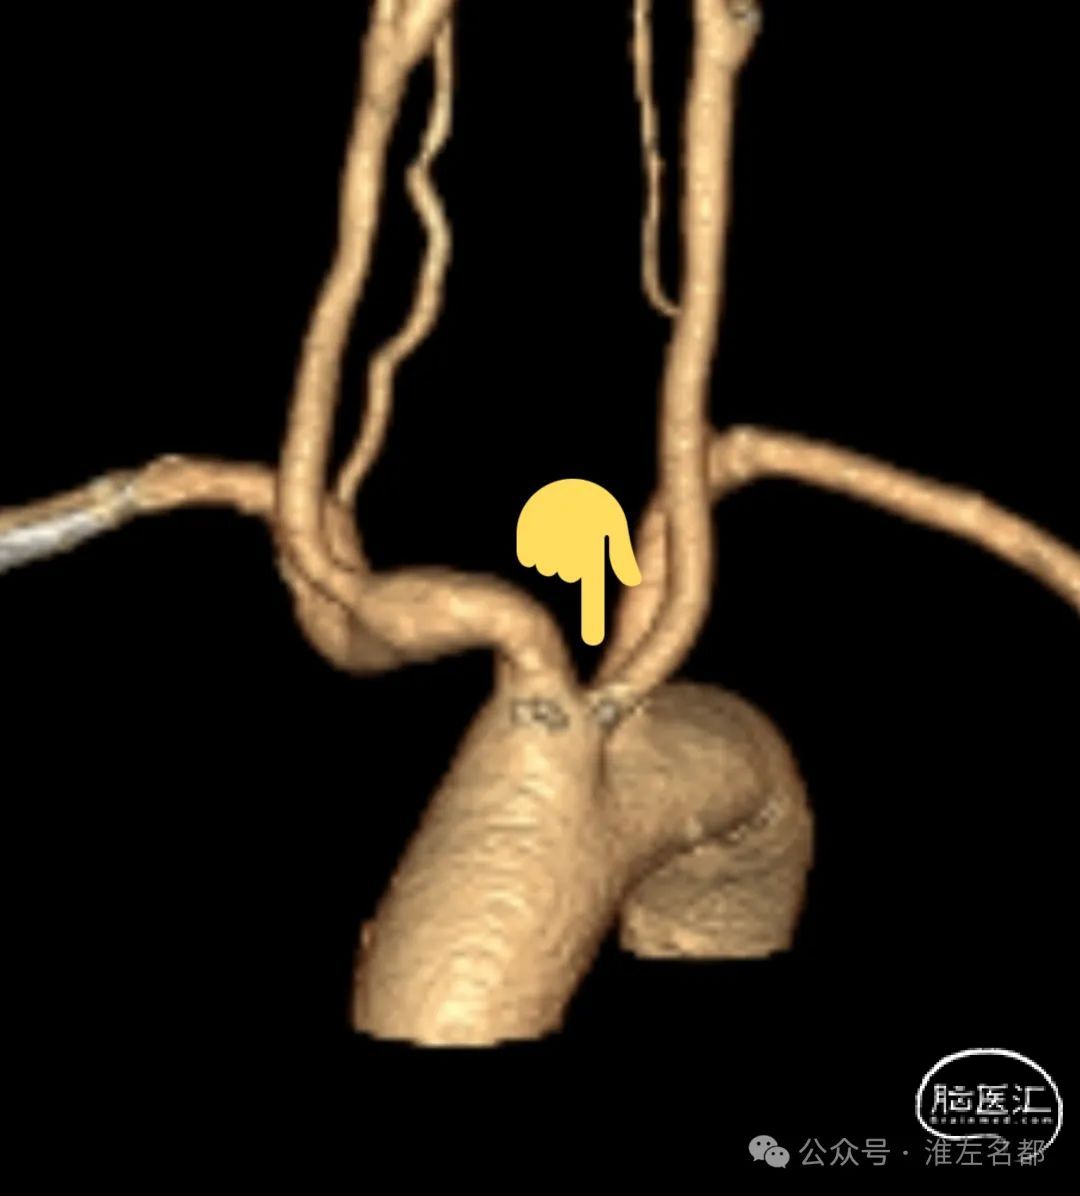

CTA:左ICA起始部重度狭窄,左CCA与无名动脉短共干,左CCA起始段走行明显向左,与主动脉弓呈显著锐角。